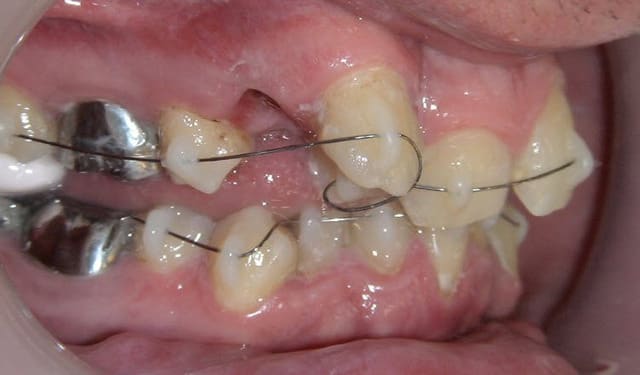

contrôle à 1 mois du cas numero 2. Tout marche comme prévu. Encore mille mercis Daniel. Ta technique a beaucoup plus à mes confrères suédois !

Cas nr 2 controle  1mois kps86j - Eugenol